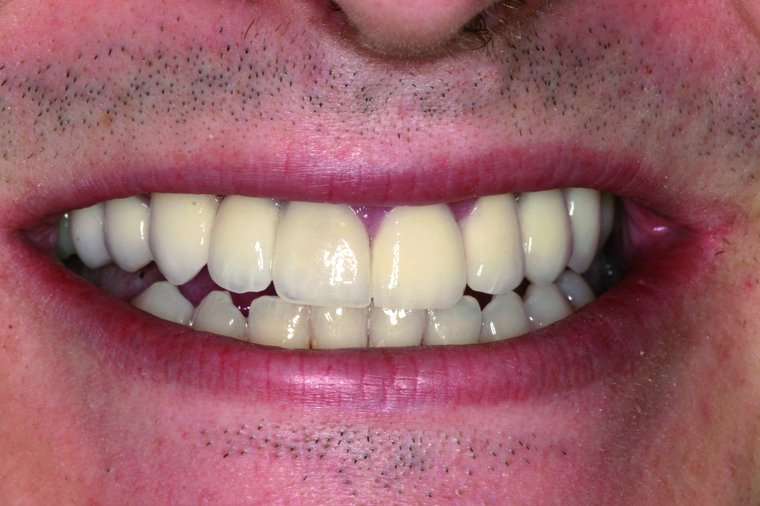

White-Is-Beautiful Konzept

- Beratung, Planung und Kostenaufstellung im ersten Termin

- Keine Wartezeiten, flexibles Zeitmanagement, Termine bis 21.00

und samstags möglich - Alle Behandlungsschritte aus einer Hand

- Eigenes Meisterlabor

- Sichere Amalgamentfernung

- Metallfreie biologische Materialien

- Schonende Behandlung in Vollnarkose

Bei einer Generalsanierung müssen alle zahnmedizinischen Bereich in Betracht gezogen werden, dies beginnt bei der Aufklärung und Prophylaxe, gefolgt von Zahnfleischbehandlungen und Kariestherapie, eventuellen Zahnentfernungen, Knochenaufbauten und wird durch ästhetischen Zahnersatz abgeschlossen. Unser Recall-System hält die erreichte Zahnsanierung über lange Jahre stabil.